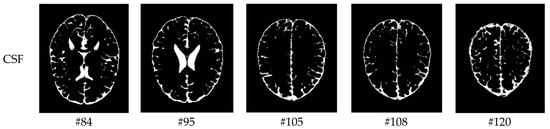

As mentioned before, the images of the first five datasets in Table 3 were used to evaluate the performance of the HMRF-WOA. Figure 1, Figure 2, Figure 3, Figure 4 and Figure 5 show some slices of a T1-weighted image (slices: 84, 95, 105, 108, 120). These brain images correspond to the slices under different types of conditions, such as database type, dimension image, noise level, intensity non-uniformity level, and slice thickness (mm). In Table 1, rows 1 to 5 summarize the parameters of Figure 1, Figure 2, Figure 3, Figure 4 and Figure 5, respectively. Figure 6 represents the ground truth segmentation of slices 84, 95, 105, 108, and 120. In this figure, each column contains the three tissues, GM, WM, and CSF, of each slice. Figure 7, Figure 8, Figure 9, Figure 10 and Figure 11 show the segmentation results, where the four tissues (BG, GM, WM, and CSF) are shown with different colors. The yellow, red, and green colors represent the segmented regions of GM, WM, and CSF, respectively. As we can also see from these figures, the resulting segmented images in Figure 7, Figure 8, Figure 9, Figure 10 and Figure 11 are almost close to the initial images in Figure 1, Figure 2, Figure 3, Figure 4 and Figure 5.

Figure 1. Slices with Noise = 0%, INU = 0% of database 1.

Figure 6. Ground truth segmentation of the GM, WM, and CSF tissues.